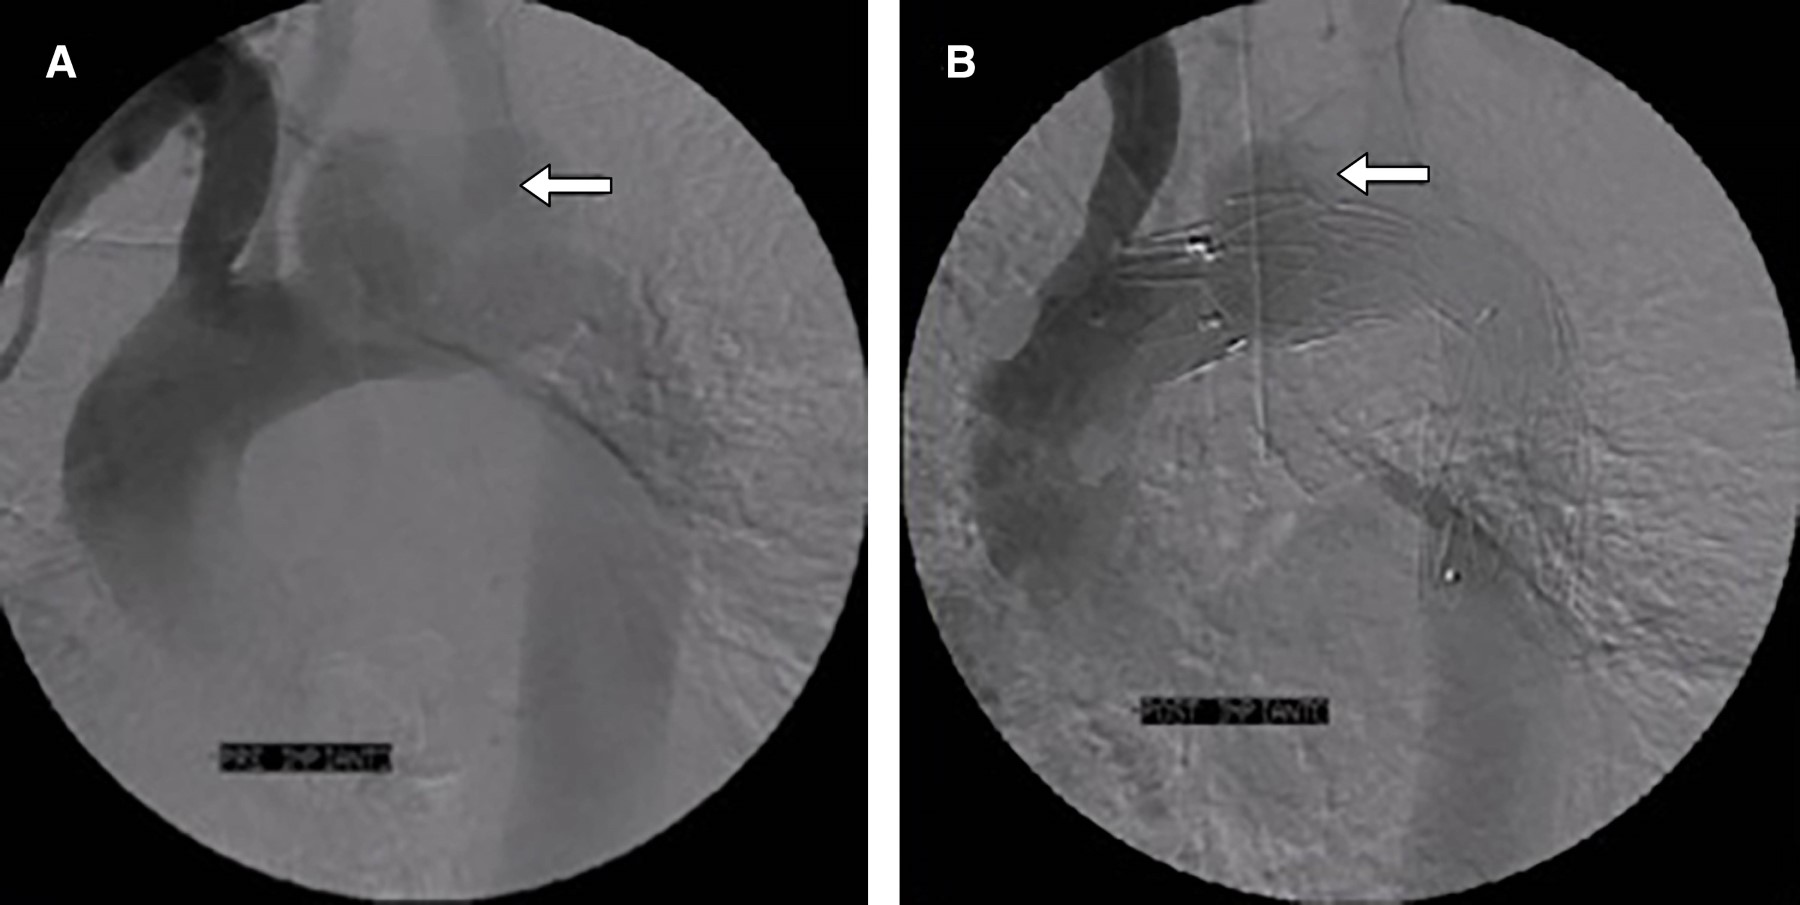

Figura 2